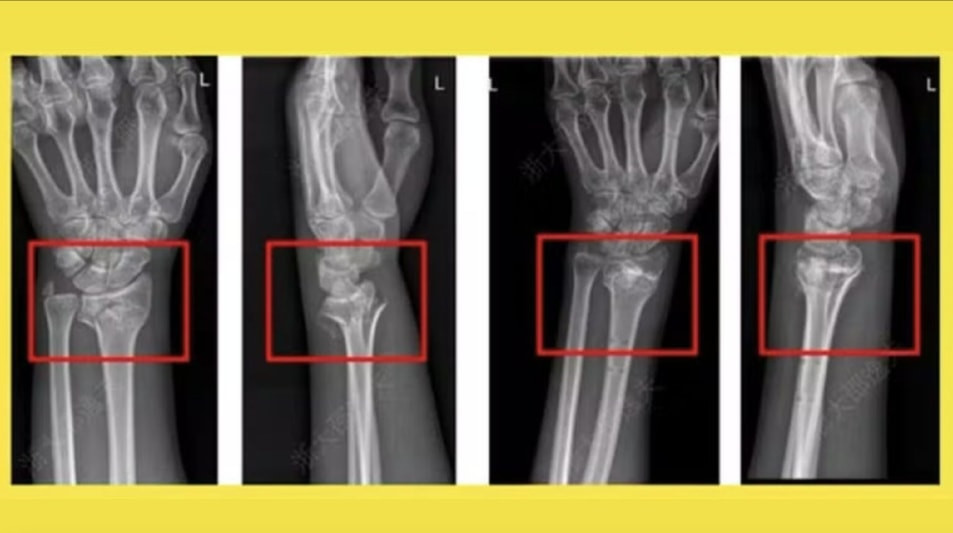

Một trong những trường hợp điển hình là bệnh nhân bị gãy cổ tay do tai nạn sinh hoạt. Thay vì phải phẫu thuật đặt nẹp kim loại, bác sĩ chỉ rạch một đường nhỏ dài khoảng 3 cm rồi tiêm Bone-02 vào vị trí gãy. Toàn bộ quá trình chỉ kéo dài vài phút, và sau ba tháng, xương đã liền hoàn toàn, không cần can thiệp thêm. Đặc biệt, bệnh nhân không gặp biến chứng hay phản ứng phụ nào, điều thường thấy ở các ca cấy ghép kim loại.